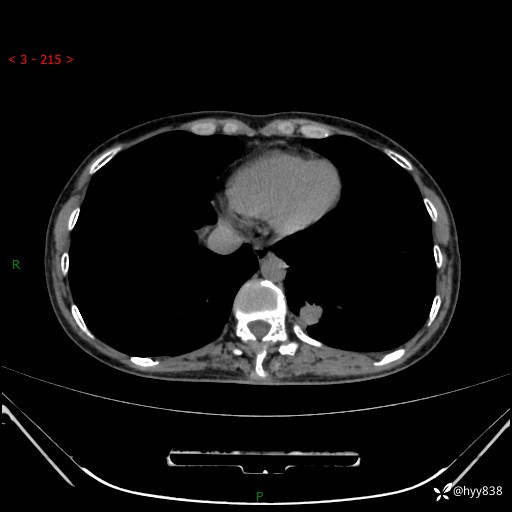

增强动脉期+静脉期

各期CT值:48hu 65hu 76hu